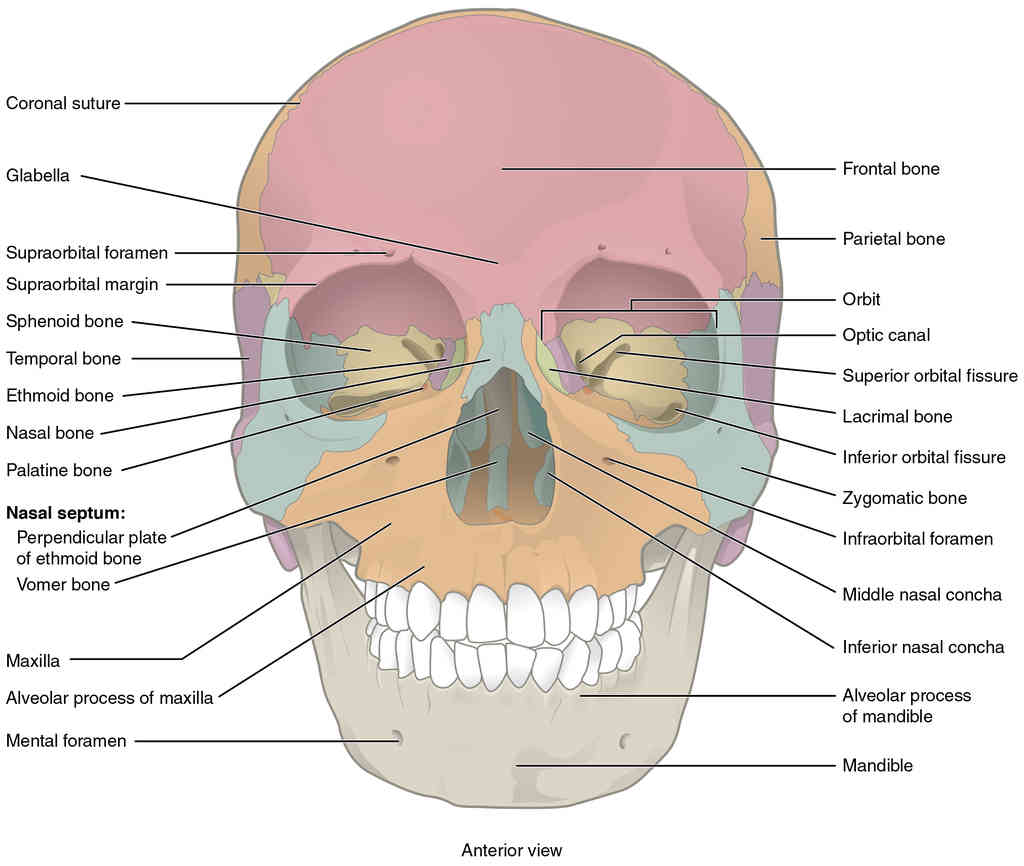

This page is under construction. For now, it is just a resource of the images found in the OpenStax Anatomy and Physiology Handbook. It wil slowly change into a revision tool. Each slide has a number. Use this to refer to the slide. When completed, it will have an unlabelled section, with labelled slides in parallel. On the unlabelled slides, write your answer and use the labelled slide to assess yourself. Keep track by also noting the number on each slide. Improvement at each attempt is important, more so than full marks on a first attempt.